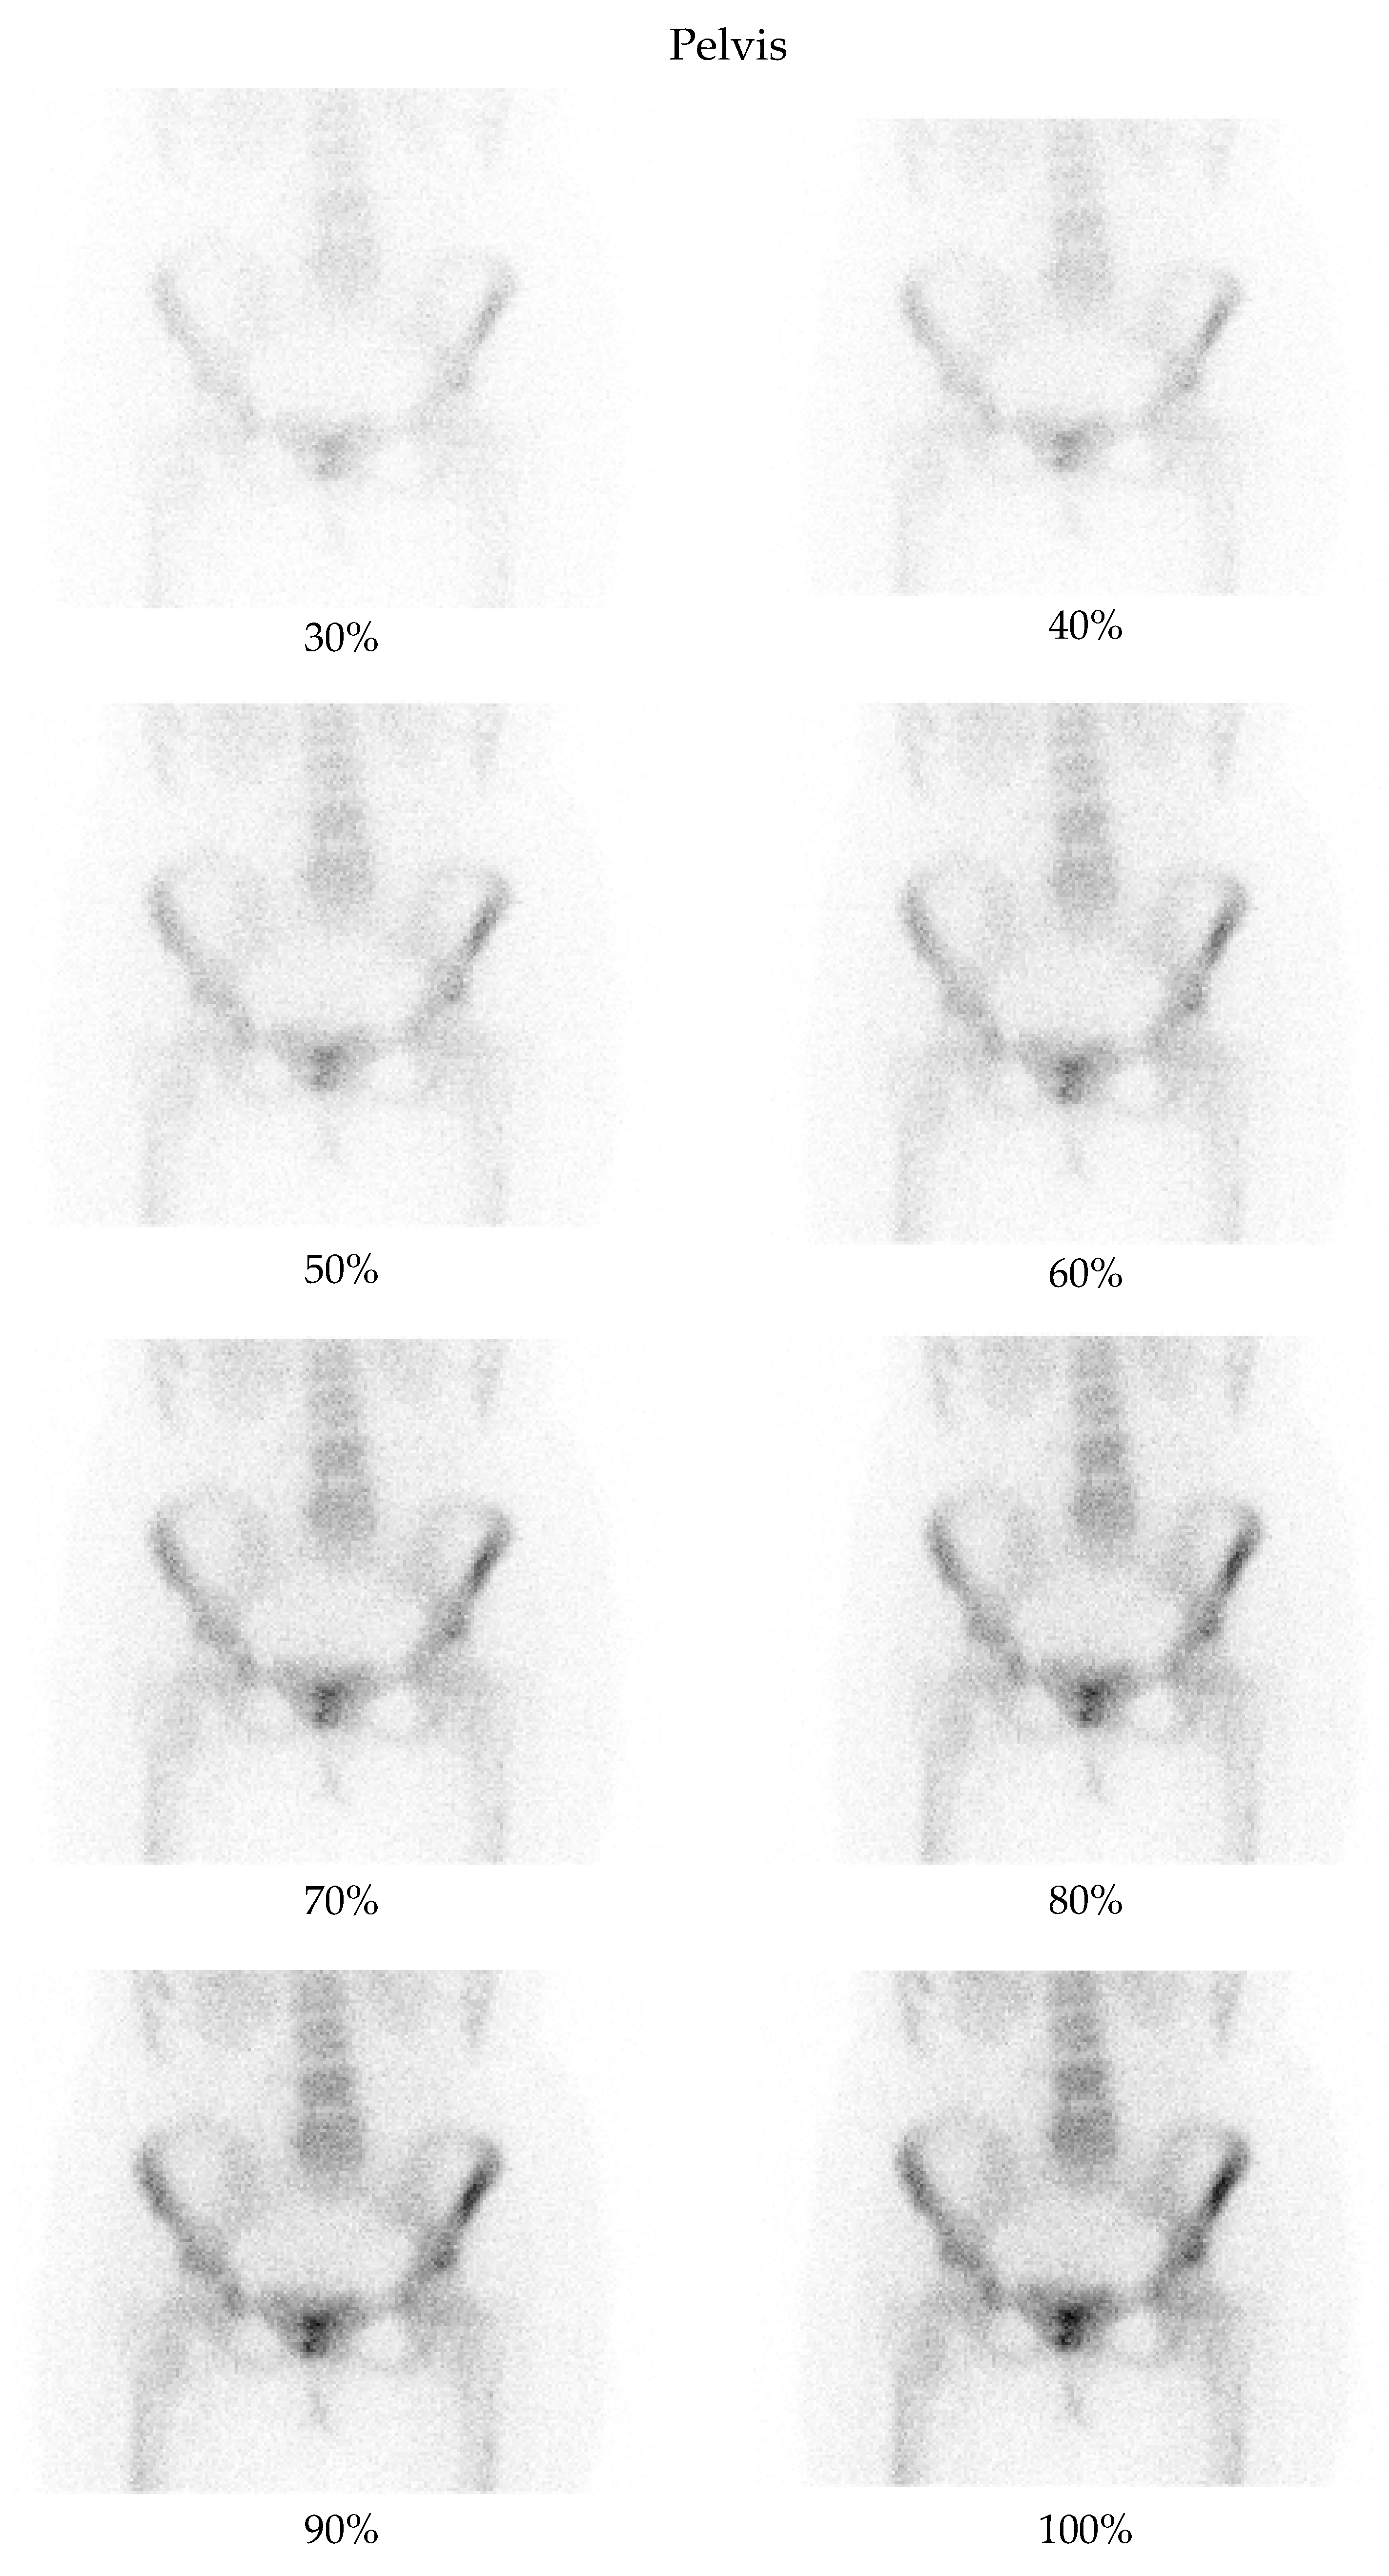

3.2. Qualitative Evaluation

- Pelvis at a 50% dose: 90.48% of comparisons favored the denoised image.